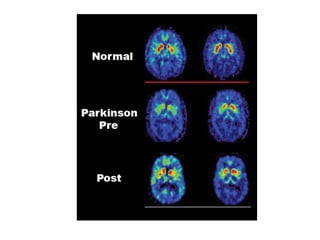

Enfermedad de Parkinson

• Temblor

• Rigidez

• Bradicinesia

• Trastornos posturales.

Fisiopatología